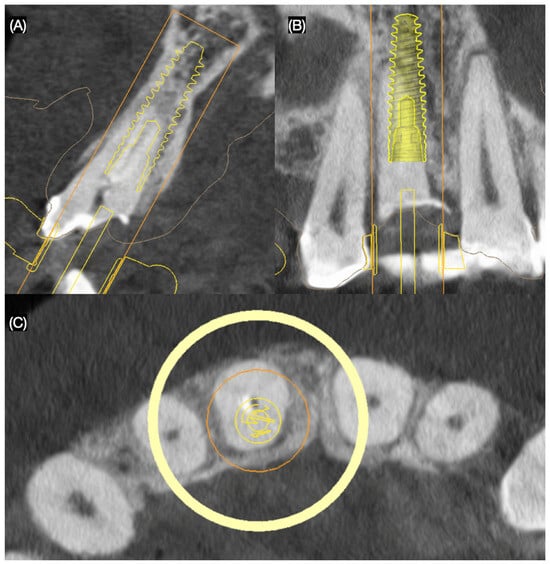

Based on clinical and radiographic findings, the patient was diagnosed with the following: A non-restorable, fractured maxillary right central incisor; old and stained resin composite restorations on both maxillary lateral incisors; and incisal wear on the maxillary canines, lateral incisors, and left central incisor. The patient was informed that due to the extent and location of the fracture, the maxillary right central incisor could not be salvaged and required extraction. A comprehensive treatment plan was proposed to address the patient’s functional and esthetic concerns, including the replacement of the non-restorable tooth and the enhancement of the anterior dentition. The plan consisted of the placement of a single immediate implant to replace the fractured maxillary right central incisor and ceramic veneers for the maxillary right lateral incisor, left lateral incisor, right canine, and left canine. A three-dimensional cone-beam computed tomography implant evaluation was also conducted (MSOFT, MIS Implant, Misgav, Israel) to assess the structural condition of the affected tooth and surrounding tissues. The evaluation revealed a subgingival horizontal fracture of the maxillary right central incisor (Figure 2).

Figure 2.

Three-dimensional implant evaluation with CBCT: (A) axial, (B) frontal, and (C) incisal view.

Considering the patient’s financial constraints and preferences, she opted for ceramic veneers for the maxillary lateral incisors and a resin composite veneer solution for both canines. To visualize the proposed outcomes, a diagnostic printed (Anycubic Resin 3D Printer Mono 4K, Anycubic, Shenzhen, China) was fabricated based on the patient’s intraoral scan. A traditional wax-up (Anycubic Clear UV Resin, Anycubic, Shenzhen, China) was created on the printed diagnostic model to refine and communicate the desired anatomy of the anterior dentition. The goal of digitally planning the immediate implant placement was to position it 3 mm apical to the crestal bone to achieve initial stability, as recommended in the literature [25,26]. Additionally, a three-dimensional evaluation was conducted to ensure precise treatment planning, and a surgical guide was designed (MSOFT, MIS Implant, Misgav, Israel) to facilitate accurate implant placement (Figure 3).